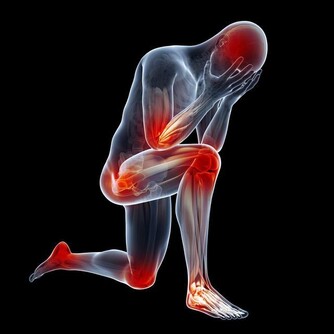

進而形成尿酸鹽結晶,沉積在關節內,造成關節疼痛及腫脹。

中醫師黃慧娟表示,痛風患者應盡量服用清熱利濕的飲食,就中醫來說,

木瓜具有祛風溼、消腫、舒經活絡、緩解肌肉僵硬的功效,

可以幫助治療痛風、關節炎、腳氣、風濕痹痛等;